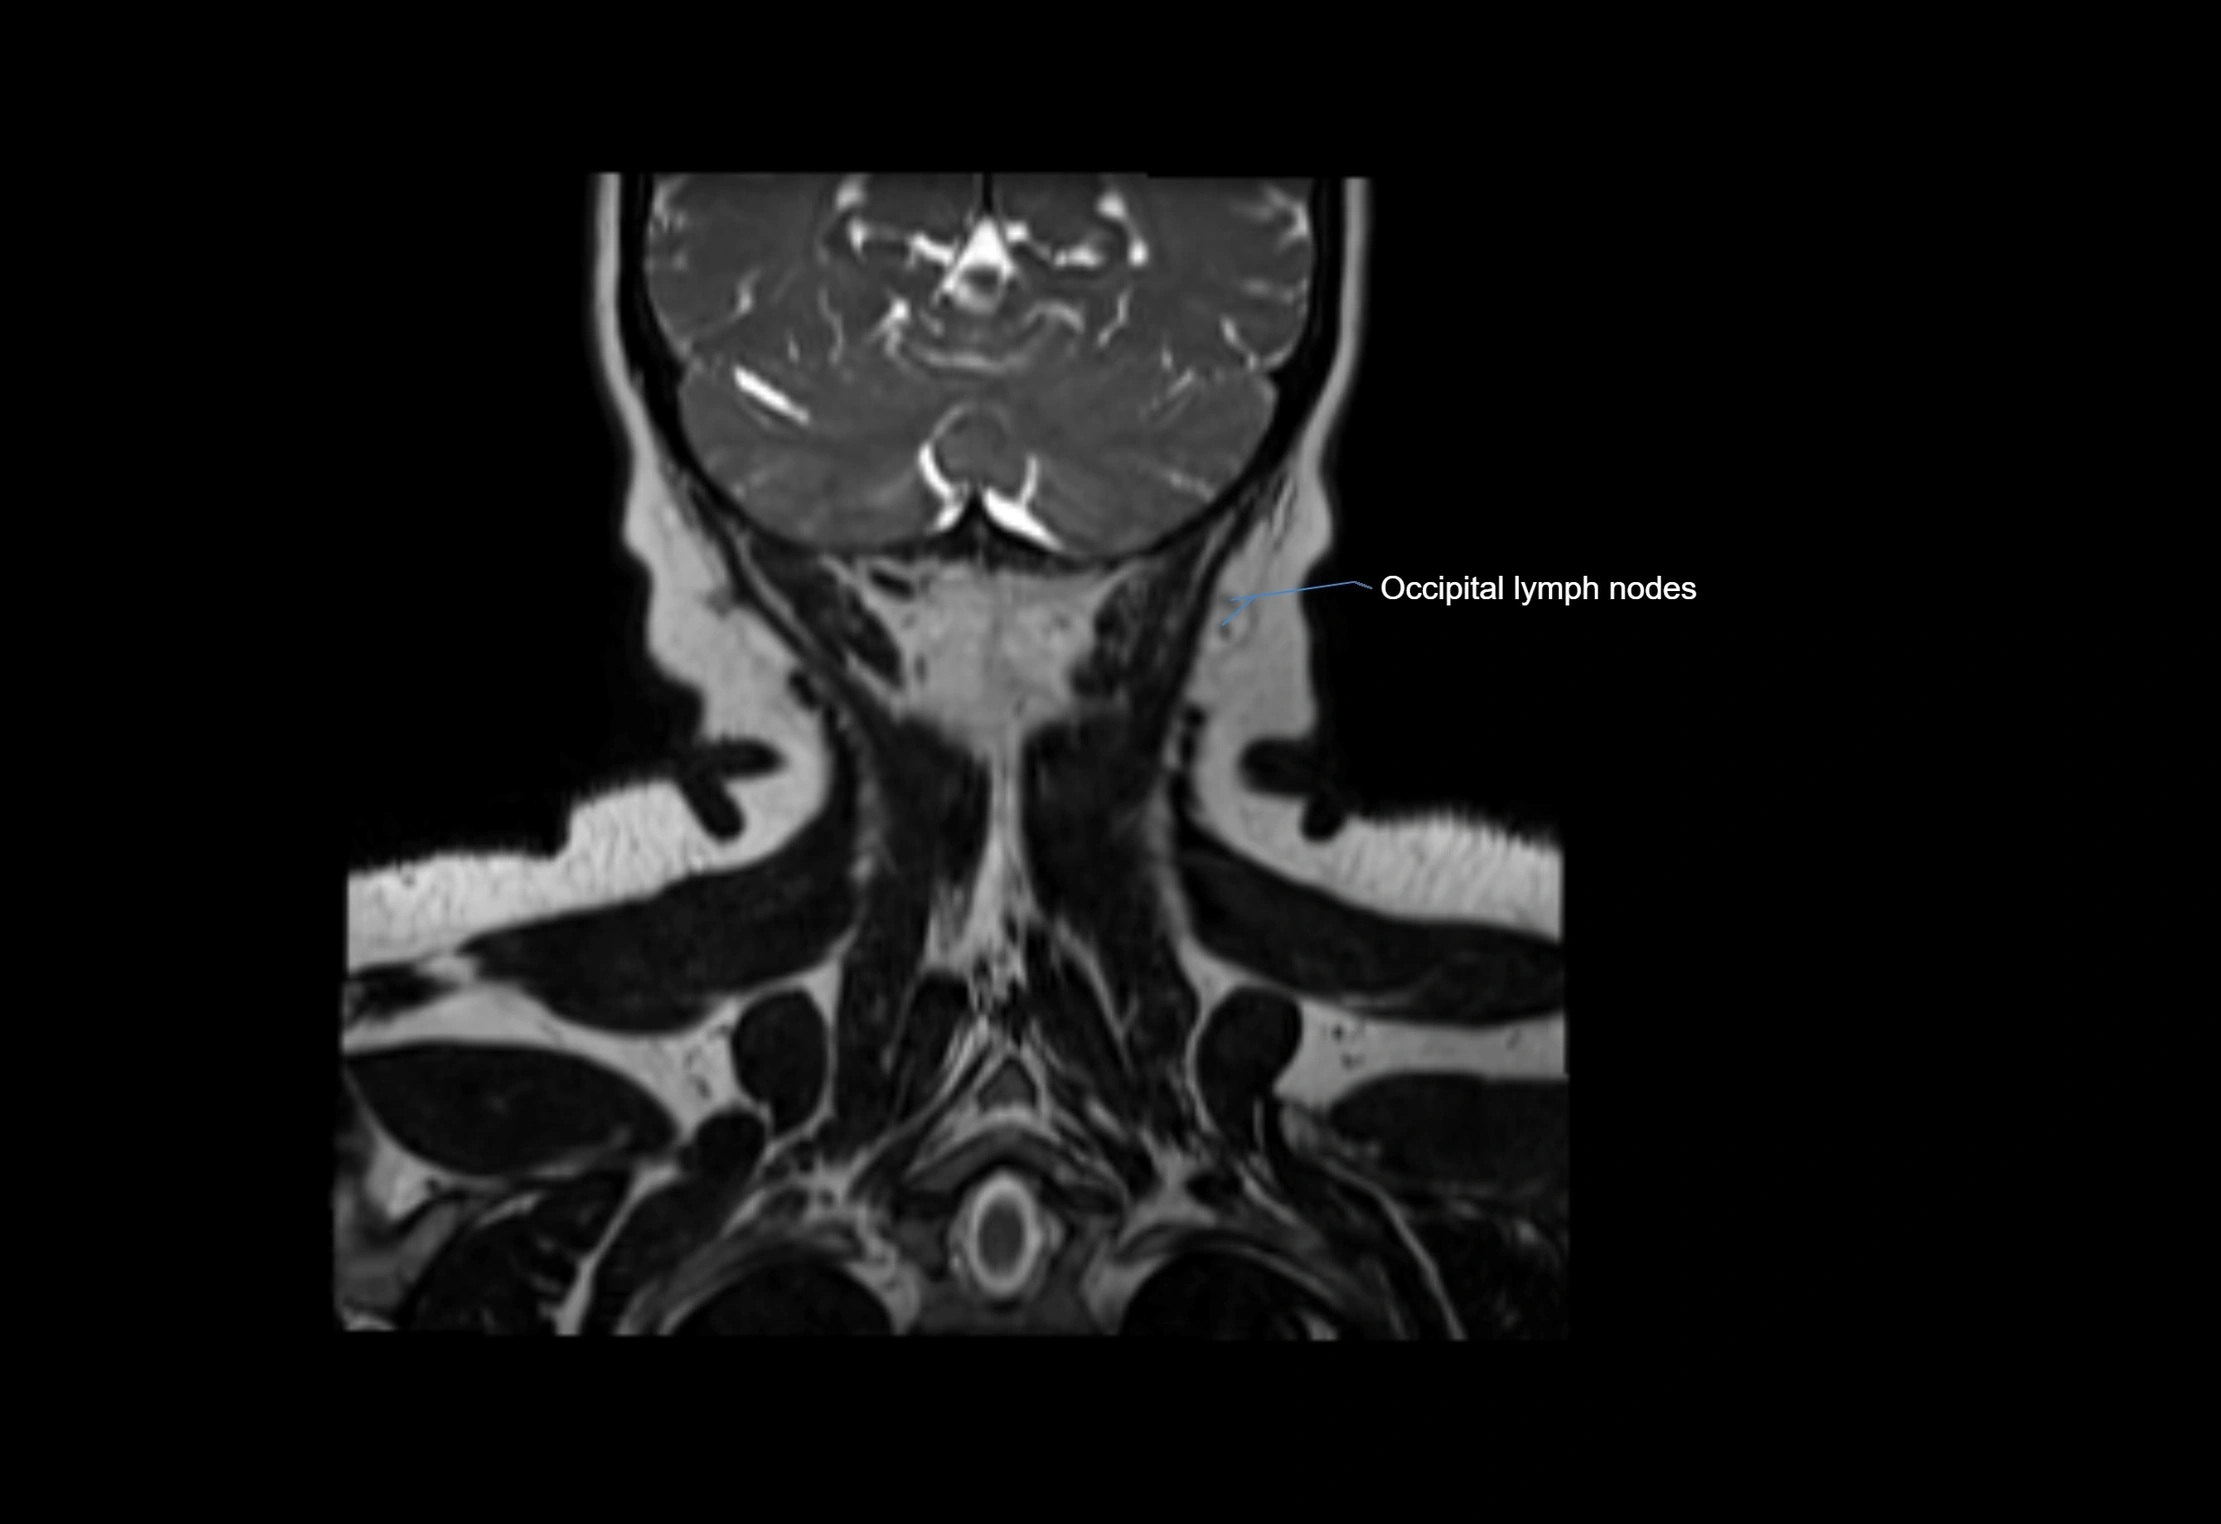

Location

• Found along primary lymph node chains, including preauricular, submandibular, parotid, and occipital regions

• Embedded in subcutaneous fat or superficial fascia, often lateral or posterior to primary nodes

MRI images

image